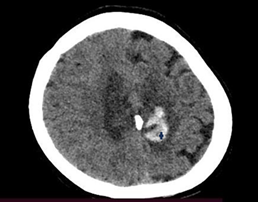

Three days later appears in new CT scan two

hypodense areas at the bilateral frontoparietal level, the one on the left side

with a hyperdense image inside an attenuation range of 40-62 HU, which

constitutes the cashew nut sign, corresponding to a concave intraparenchymal

haemorrhage secondary to thrombosis of the left transverse venous sinus.

Image of a cashew nut or Indian nut (Figure

1), (Figure 2) from a single-phase cranial tomography scan.

Figure

1: Image of a cashew nut or Indian nut

2: Single-phase cranial tomography scan